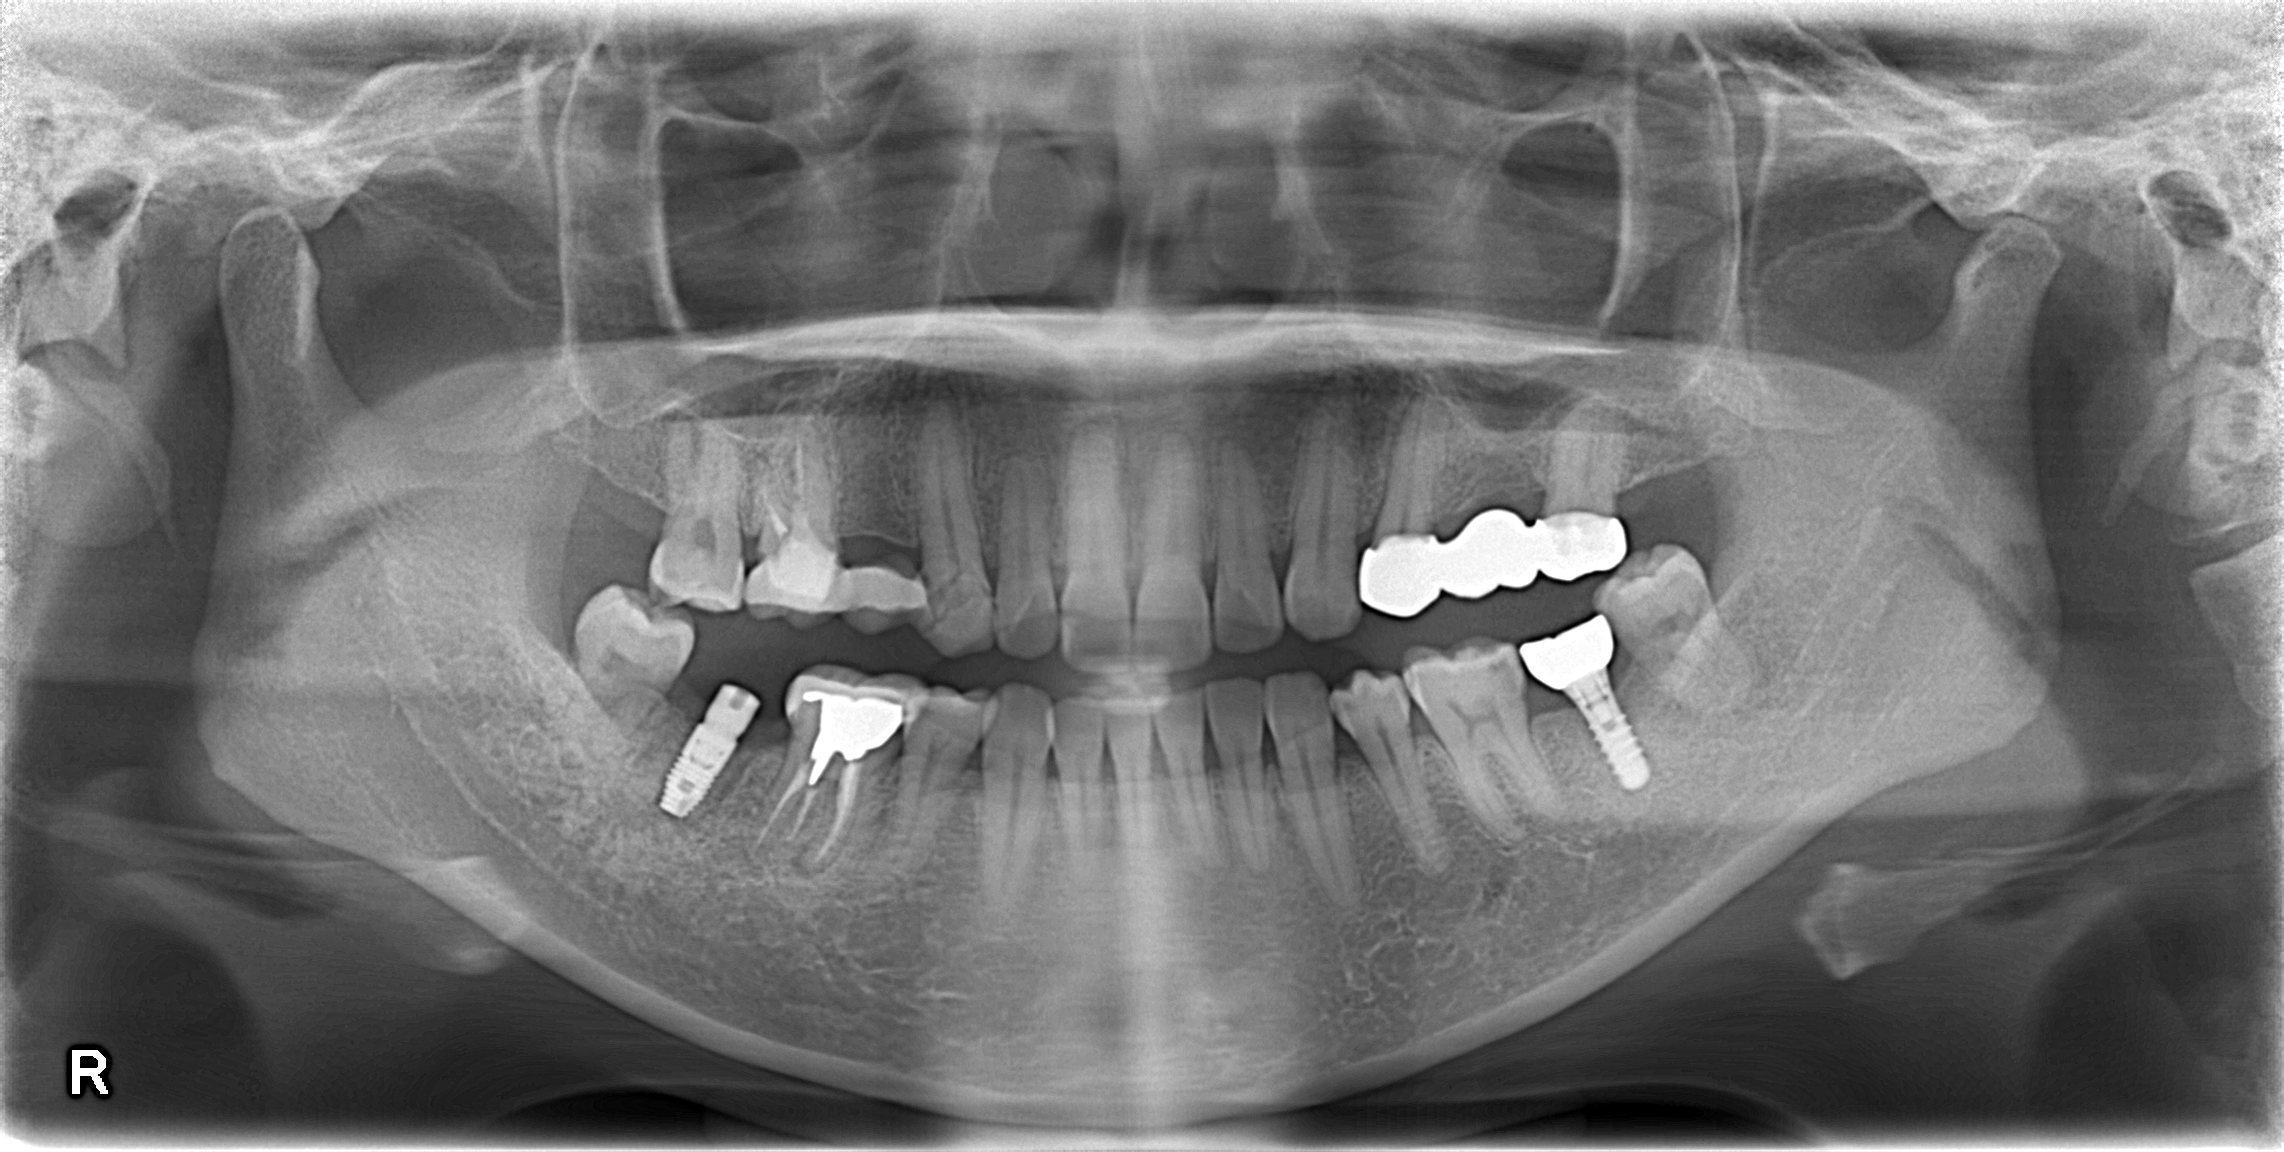

さて、先日も当院でインプラント手術行った症例をご紹介させていただきます。

📌 今回の症例について

今回の症例は、右下奥歯「7番」へのインプラント埋入でした

むし歯が重度のため保存不可能と判断し抜歯と同時に骨造成処置を行いました。

その後、骨造成された後、インプラント埋入手術を行いました。

術中・術後ともに特に問題なく、予定通りに埋入を終えることができました💡

ここから数か月かけて、インプラントと顎骨がしっかり結合する「オッセオインテグレーション🦴」を待ち、その後に最終補綴(かぶせ物治療)を行っていく予定です✨